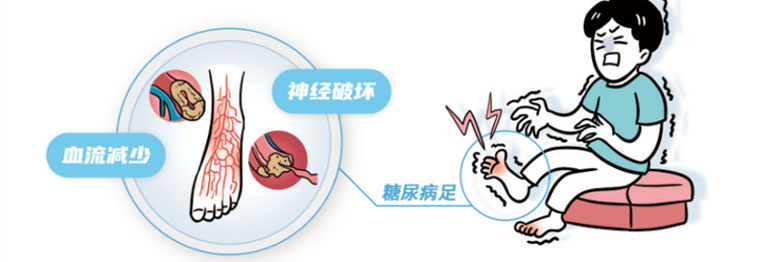

我国糖尿病患者高达1.43亿,50岁以上的糖尿病患者中,糖尿病足的发病率高达8.1%。全球每20秒就有1例糖尿病患者截肢,糖尿病足溃疡患者年死亡率达11%,而截肢患者死亡率达22%。糖尿病足的主要原因是下肢血管病变、神经病变和感染损伤,由糖尿病下肢血管病变引起的足部缺血是其最主要原因,85%的非创伤性下肢截肢是由糖尿病下肢血管病变引发的足溃疡所引起。天气寒冷时,下肢血管收缩、痉挛,会加重缺血,从而引发无力、足部疼痛、水肿、发黑、腐烂、坏死,导致截肢甚至有生命危险。

糖尿病可引起全身血管病变,通常人们更多关注于心脑血管并发症,殊不知,糖尿病性血管病变绝大部分发生在下肢。下肢动脉粗长,承受血液压力大,内膜损伤机会多。当糖尿病患者出现心脑血管并发症时,下肢血管病变已经很严重了。当人们一旦出现胸闷、心慌、气短或心前区疼痛时自然会想到心血管疾病(冠心病);一旦出现头晕、头痛、一侧肢体活动不利、言语不清,自然会想到脑血管病,都会及时就诊,及时治疗。而当患者出现下肢无力、酸痛、抽筋、间歇性跛行甚至静息痛时,却常常会认为岁数大了走路慢是正常现象,因此错过最佳治疗时机。群众对糖尿病下肢血管病变的认识和警惕性亟待提高。